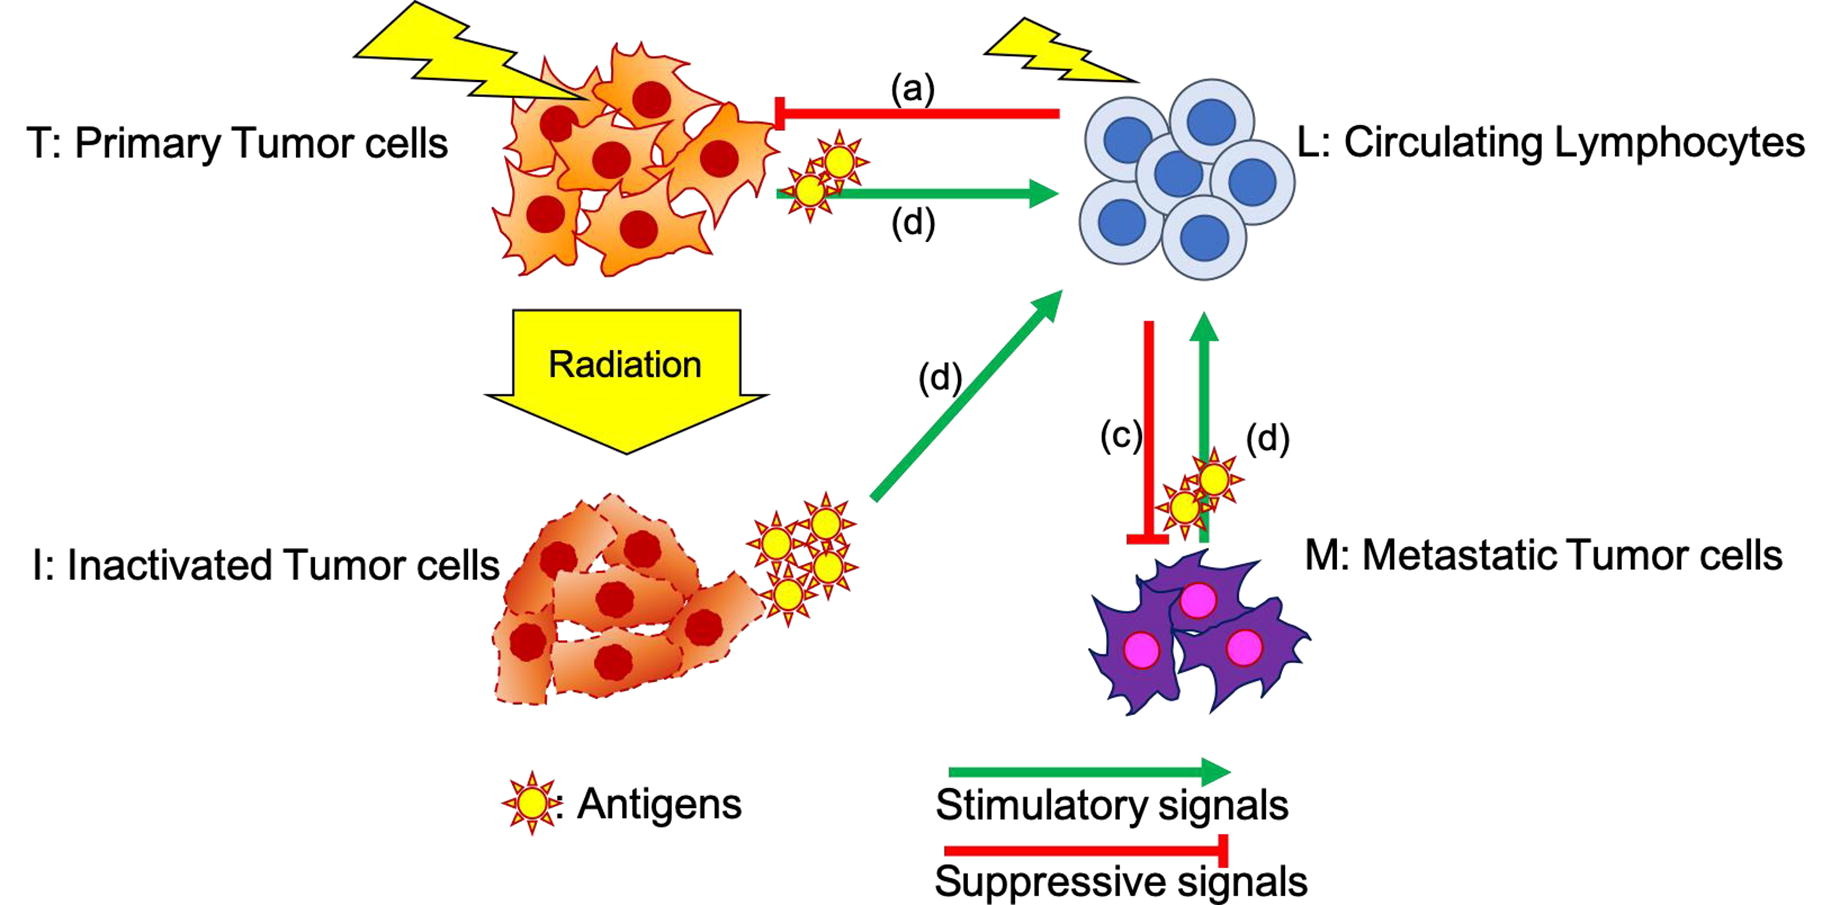

The impact of radiation therapy on the immune system has recently gained attention particularly when delivered in combination with immunotherapy. However, it is unclear how different treatment fractionation regimens influence the interaction between the immune system and radiation. The goal of this work was to develop a mathematical model that quantifies both the immune stimulating as well as the immunosuppressive effects of radiotherapy and simulates the effects of different fractionation regimens based on patient data.

The framework describes the temporal evolution of tumor cells, lymphocytes, and inactivated dying tumor cells releasing antigens during radiation therapy, specifically modeling how recruited lymphocytes inhibit tumor progression. The parameters of the model were partly taken from the literature and in part extracted from blood samples (circulating lymphocytes: CLs) collected from hepatocellular carcinoma patients undergoing radiotherapy and their outcomes. The dose volume histograms to circulating lymphocytes were calculated with a probability-based model.

Based on the fitted parameters, the model enabled a study into the depletion and recovery of CLs in patients as a function of fractionation regimen. Our results quantify the ability of short fractionation regimens to lead to shorter periods of lymphocyte depletion and predict faster recovery after the end of treatment. The model shows that treatment breaks between fractions can prolong the period of lymphocyte depletion and should be avoided.